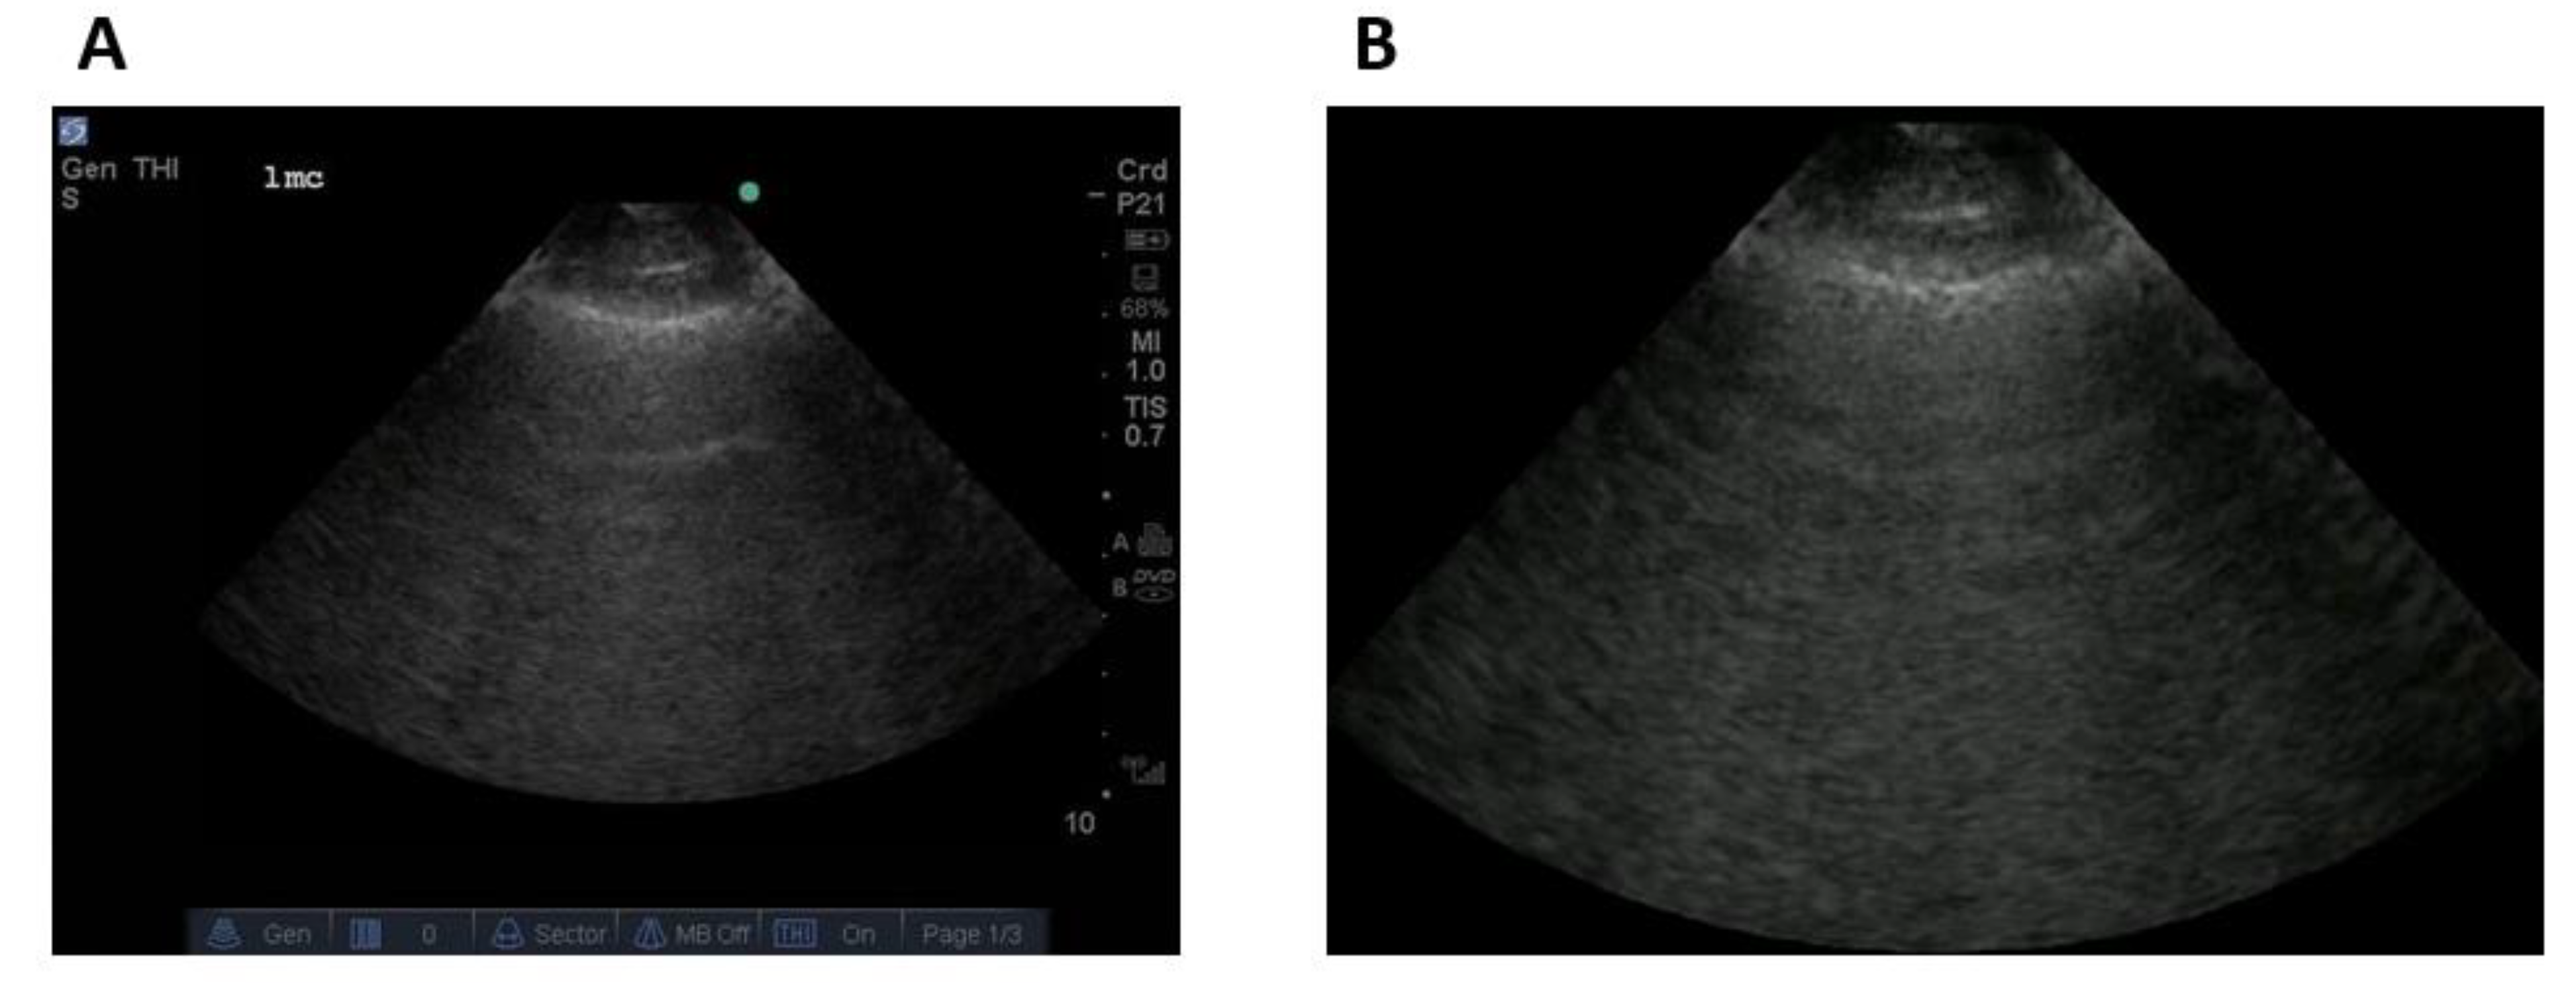

2.1.3. Data Labelling

2.2. Experimental Setup

2.2.1. Frame-Based Data

2.2.4. Data Preprocessing